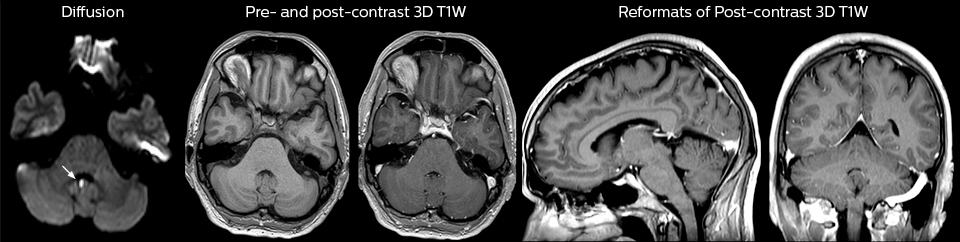

cervical spine mri in ed

Cervical spine routine exam

This patient presented with headache that was worse with neck flexion and we see a Chiari 1 malformation with low-lying cerebellar tonsils as well as some degenerative cervical thrombolytic change.